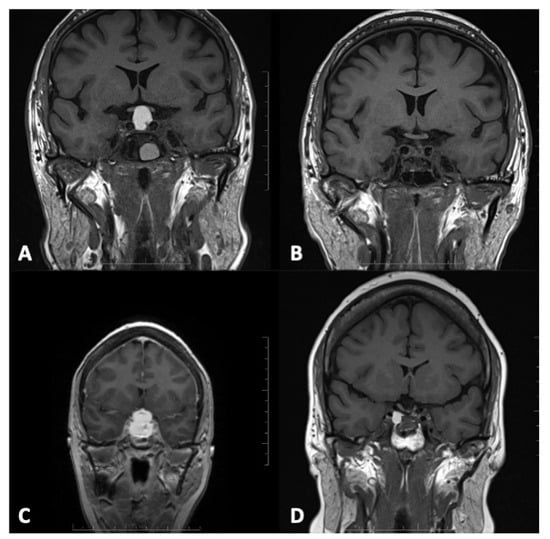

3.4. Radiological Examinations

3.5. Endonasal Endoscopic Procedures and Perioperative Complications